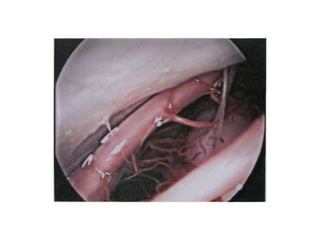

Right sided anterior petrosectomy on a cadaver dissection: intradural exposure

and operative field. PCA Petrous carotid artery; DPA drilled petrous apex; IPS

inferior petrosal sinus; BA basilar artery; VI 6th cranial nerve; AICA anterior inferior

cerebellar artery; P pons; V 5th cranial nerve

NOTE Inferior petrosal sinus at CLIVUS